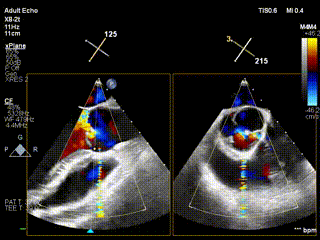

视频1:病例1术前食道超声示重度主动脉瓣反流

视频2:病例1术后心超示主动脉瓣无反流